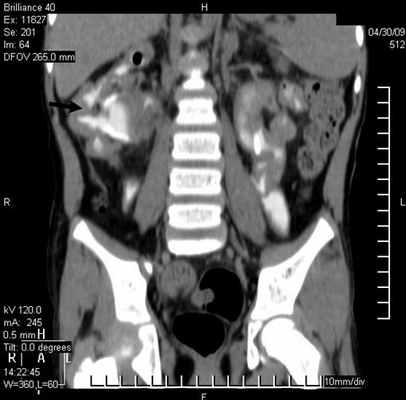

Результаты исследования и их обсуждение. Показаниями к выполнению МСКТ были расширение мочеточника. В 29 (78,4%) наблюдениях выявлен уретерогидронефроз различной степени, в 5 (13,5%) – эктопия устья мочеточников и в 3 (8,1%) - уретероцеле (рис. 1).

Болюсное введение контрастного вещества и последующее динамическое исследование различных фаз контрастирования способствует четкому выявлению уретероцеле (рис. 3б).

Уретероцеле обнаружено у 3 (8,1%) пациентов из 37. Этот порок уретеровезикального сегмента на МСКТ характеризовался с кистовидным расширением внутрипузырного сегмента мочеточника. При этом отчетливо определяется округлая полость, вдающаяся в просвет мочевого пузыря (рис. 3).

Рис 3. МСКТ картина уретероцеле. Трехмерная реконструкция. Удвоение почек и мочеточника справа (a) и уретероцеле слева (б)